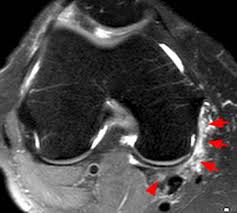

At the medial gastrocnemius tendon origin, there are 2 features of importance for mri evaluation: gastrocnemius origin and insertion. This injury occurs commonly in sports activities (eg, hill running, jumping, tennis), but it can occur in any activity.